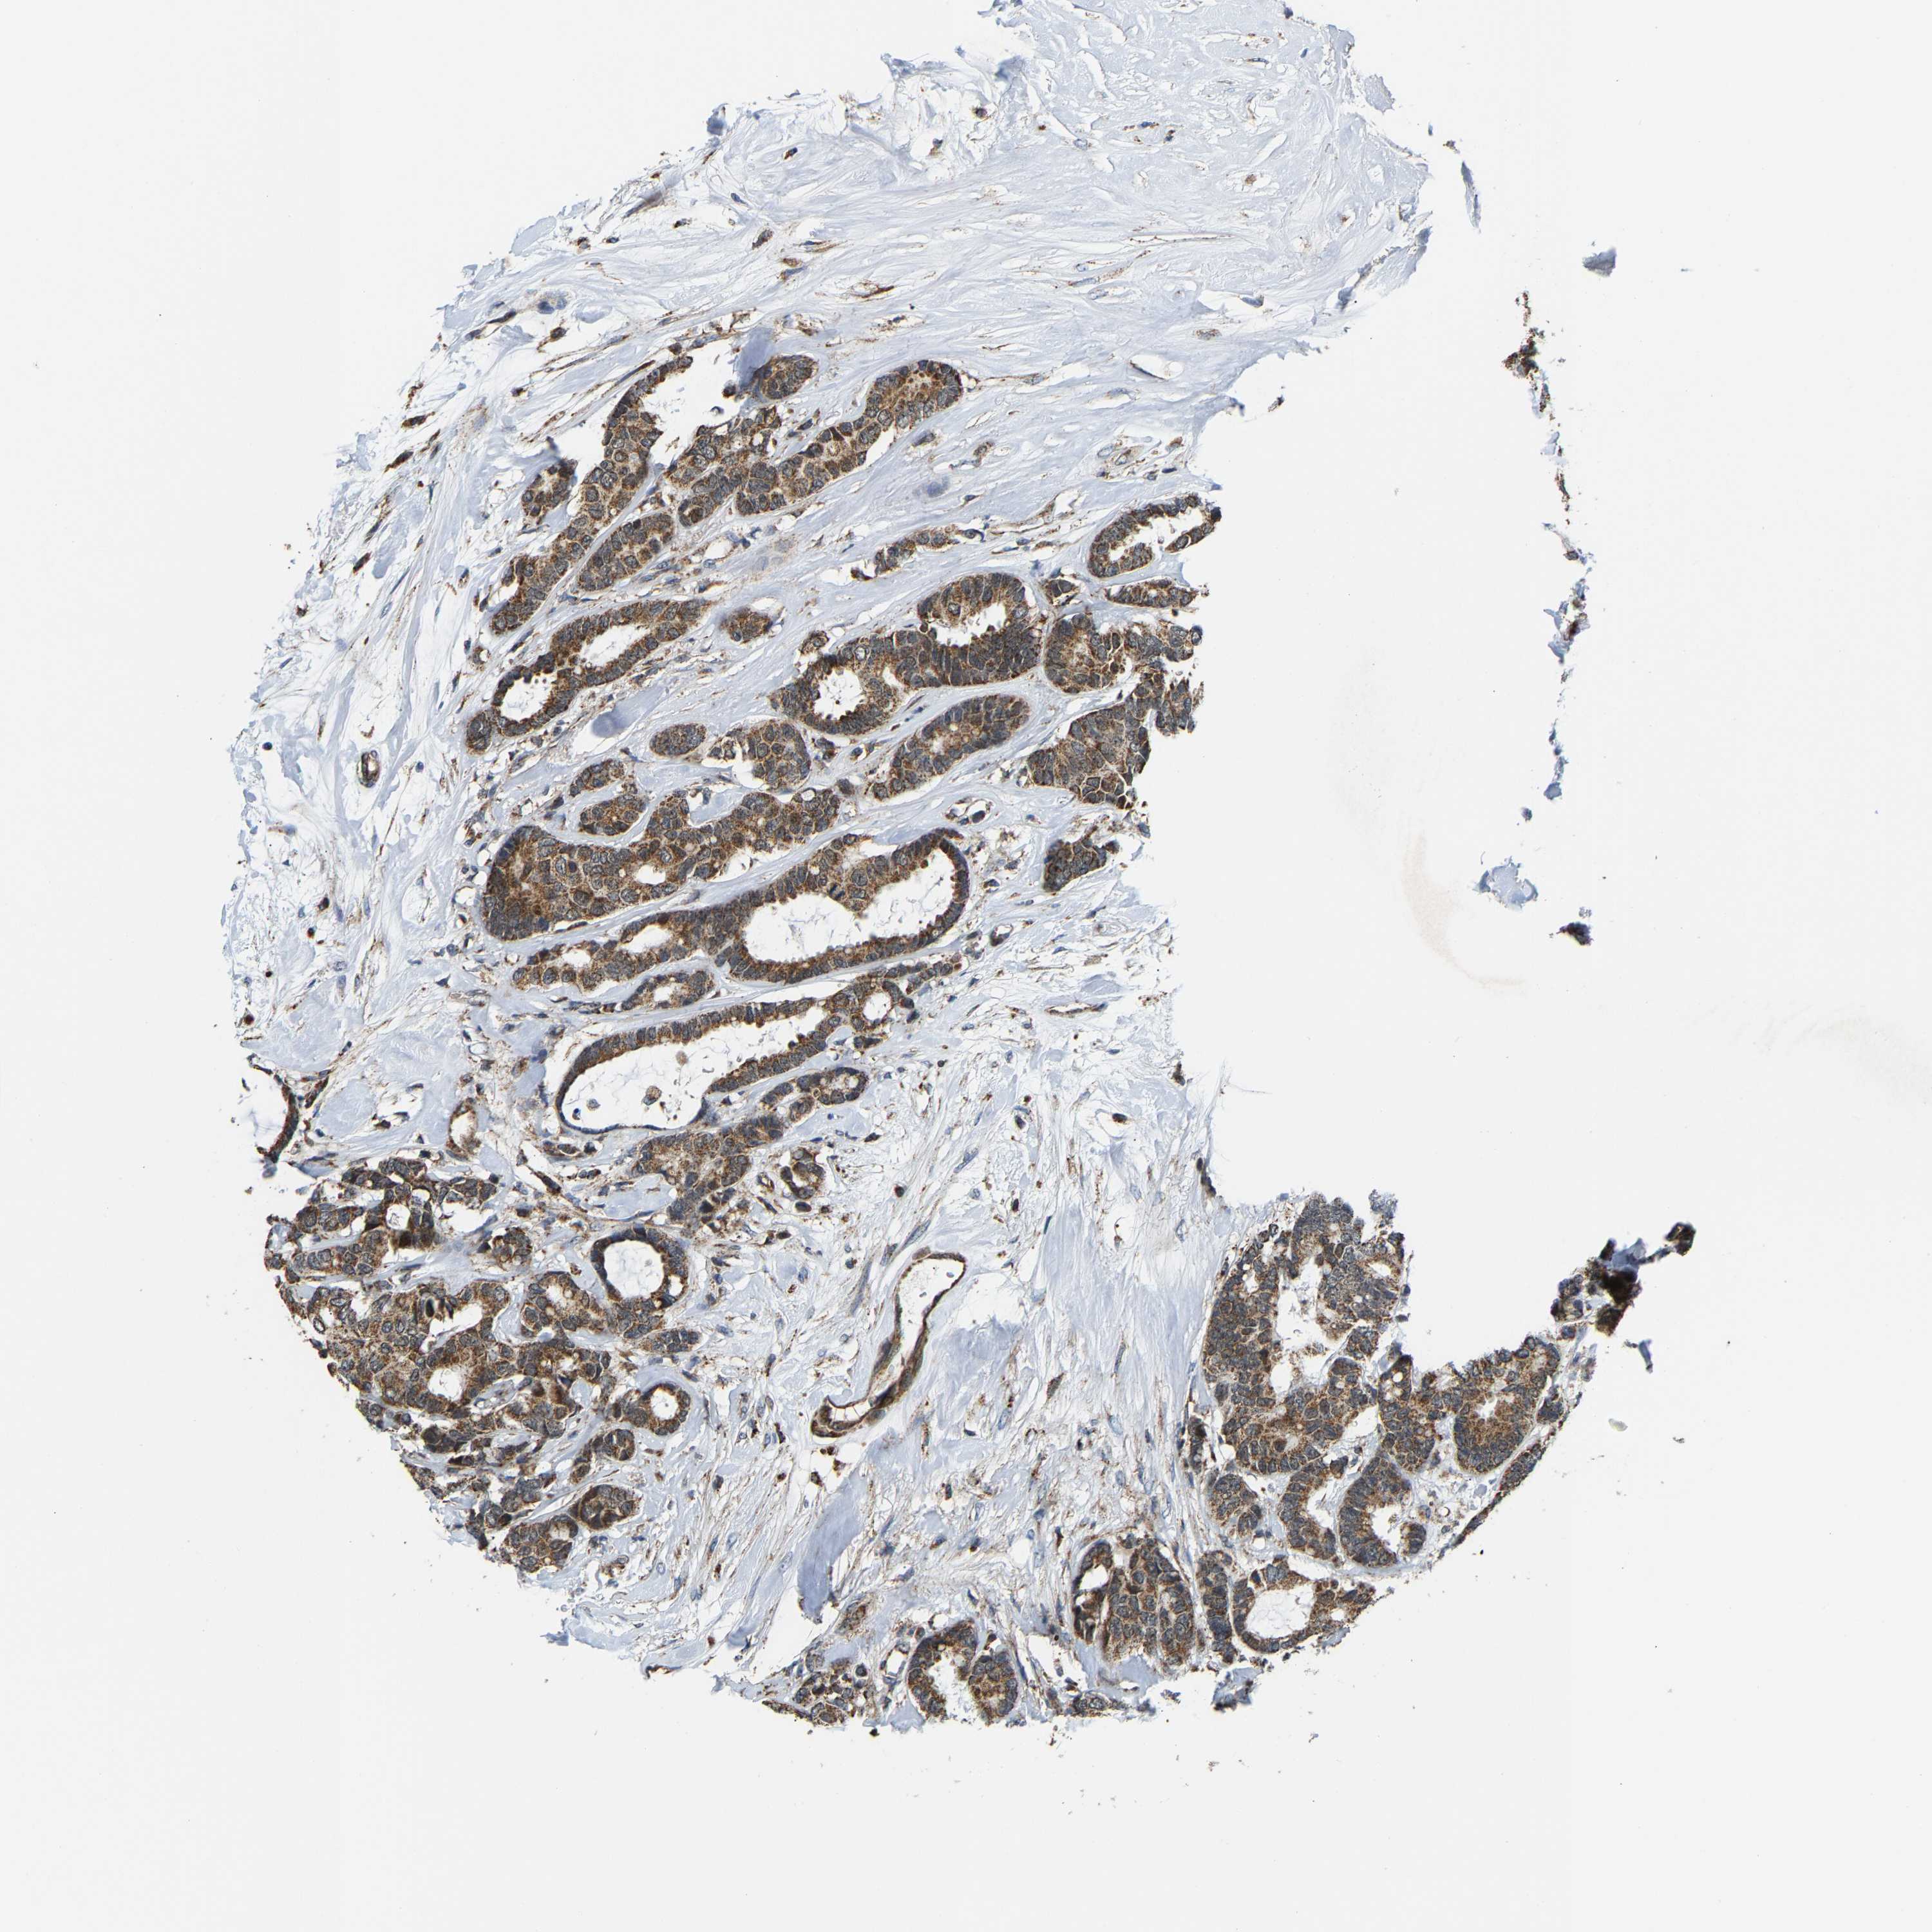

CANCER BREAST CANCER Show tissue menu

BRCA TCGA BRCA VALIDATION PROTEIN EXPRESSION

Breast cancer

Human cancer